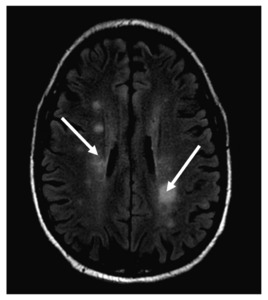

In 2013, a 66-year-old male presented with a subacute onset of left-sided weakness and tremors for one month. Blood analysis revealed a WBC of 8,000 cells/micro liter with 60% atypical lymphocytes. Subsequent examination with flow cytometry, protein electrophoresis, and bone marrow biopsy showed a monoclonal B cell population secreting IgM and lymphoplasmacytic cells in the marrow that were CD 19/CD20+ and CD5/10-, consistent with WM. Serum viscosity was 1.8 (cP; ref. range 1.4-1.8 cp), indicating that these neurological symptoms were less likely caused by hyperviscosity. Although the CSF examination showed abnormal lymphocytes, it was a bloody tap, which raised the question on whether the cells were from the CSF or blood. An MRI of the brain showed indeterminate sub-centimeter enhancing white matter foci involving bilateral parietal lobes and periventricular regions, and punctate enhancing lesions in the cerebellum (Fig. 2). Given the hematologic and MRI findings, a diagnosis of BNS was made after; however the patient refused a brain biopsy to confirm the diagnosis. He was treated with whole brain radiation and dexamethasone, bortezomib and rituximab with a mild improvement in the neurological symptoms. The patient then moved to a different city, where his WM was observed for 5 years at another healthcare facility, with stable neurological symptoms and only mild increases in IgM levels. At that point, he was lost to follow up, and his death, of unknown causes, was reported one year later.